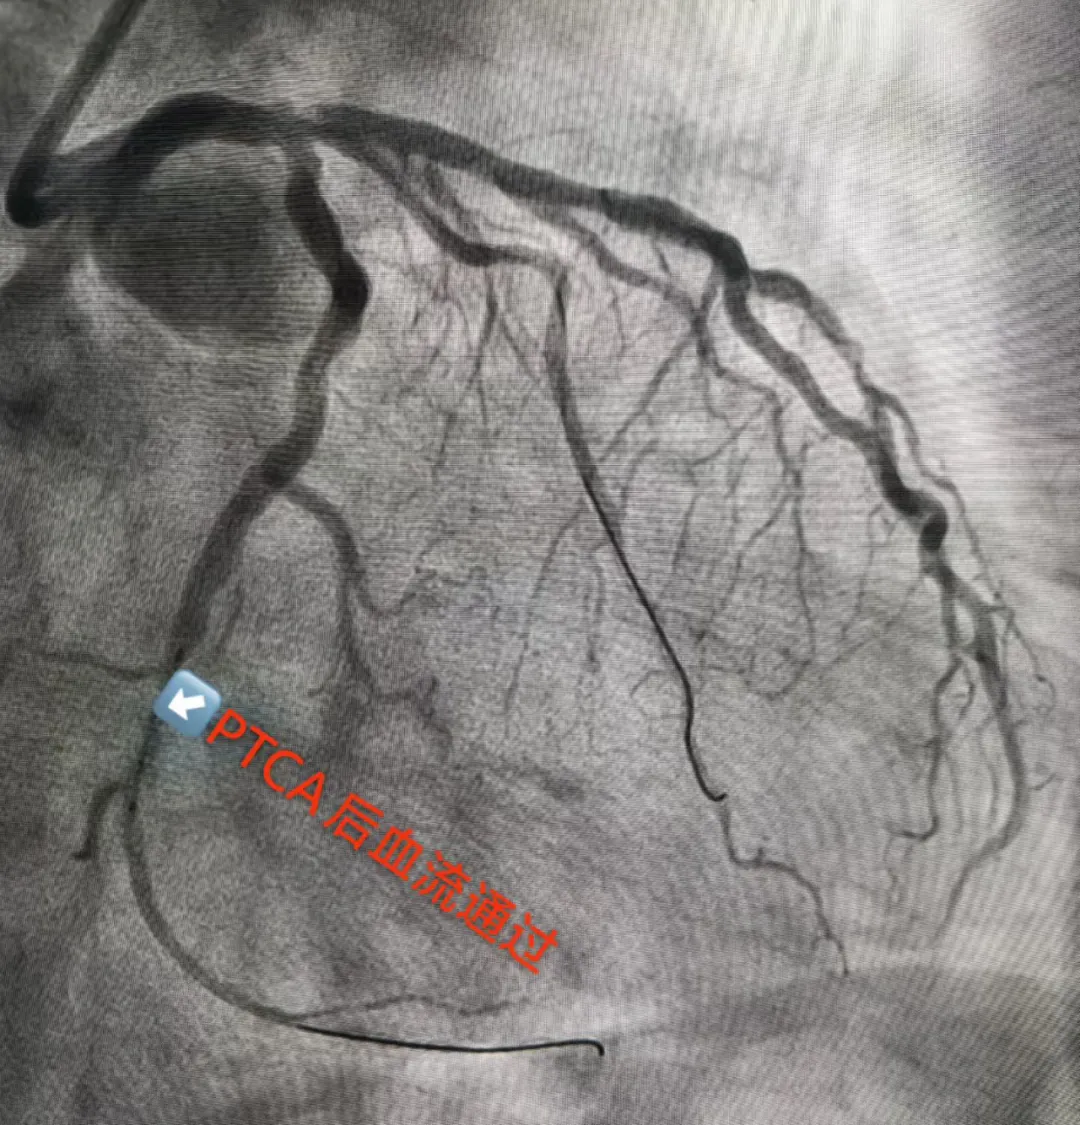

手术台上,导丝顺利通过病变部位,球囊成功扩张,闭塞血管得以开通,心肌血供逐步恢复–一切似乎正在向着预期方向发展。

然而,就在血管开通、准备植入支架的关键节点,病情陡然生变。患者突发心室颤动,身体抽搐,意识瞬间丧失。心室颤动是最危急的心律失常,意味着心脏失去有效泵血功能,若不及时纠正,数分钟内即可导致死亡。